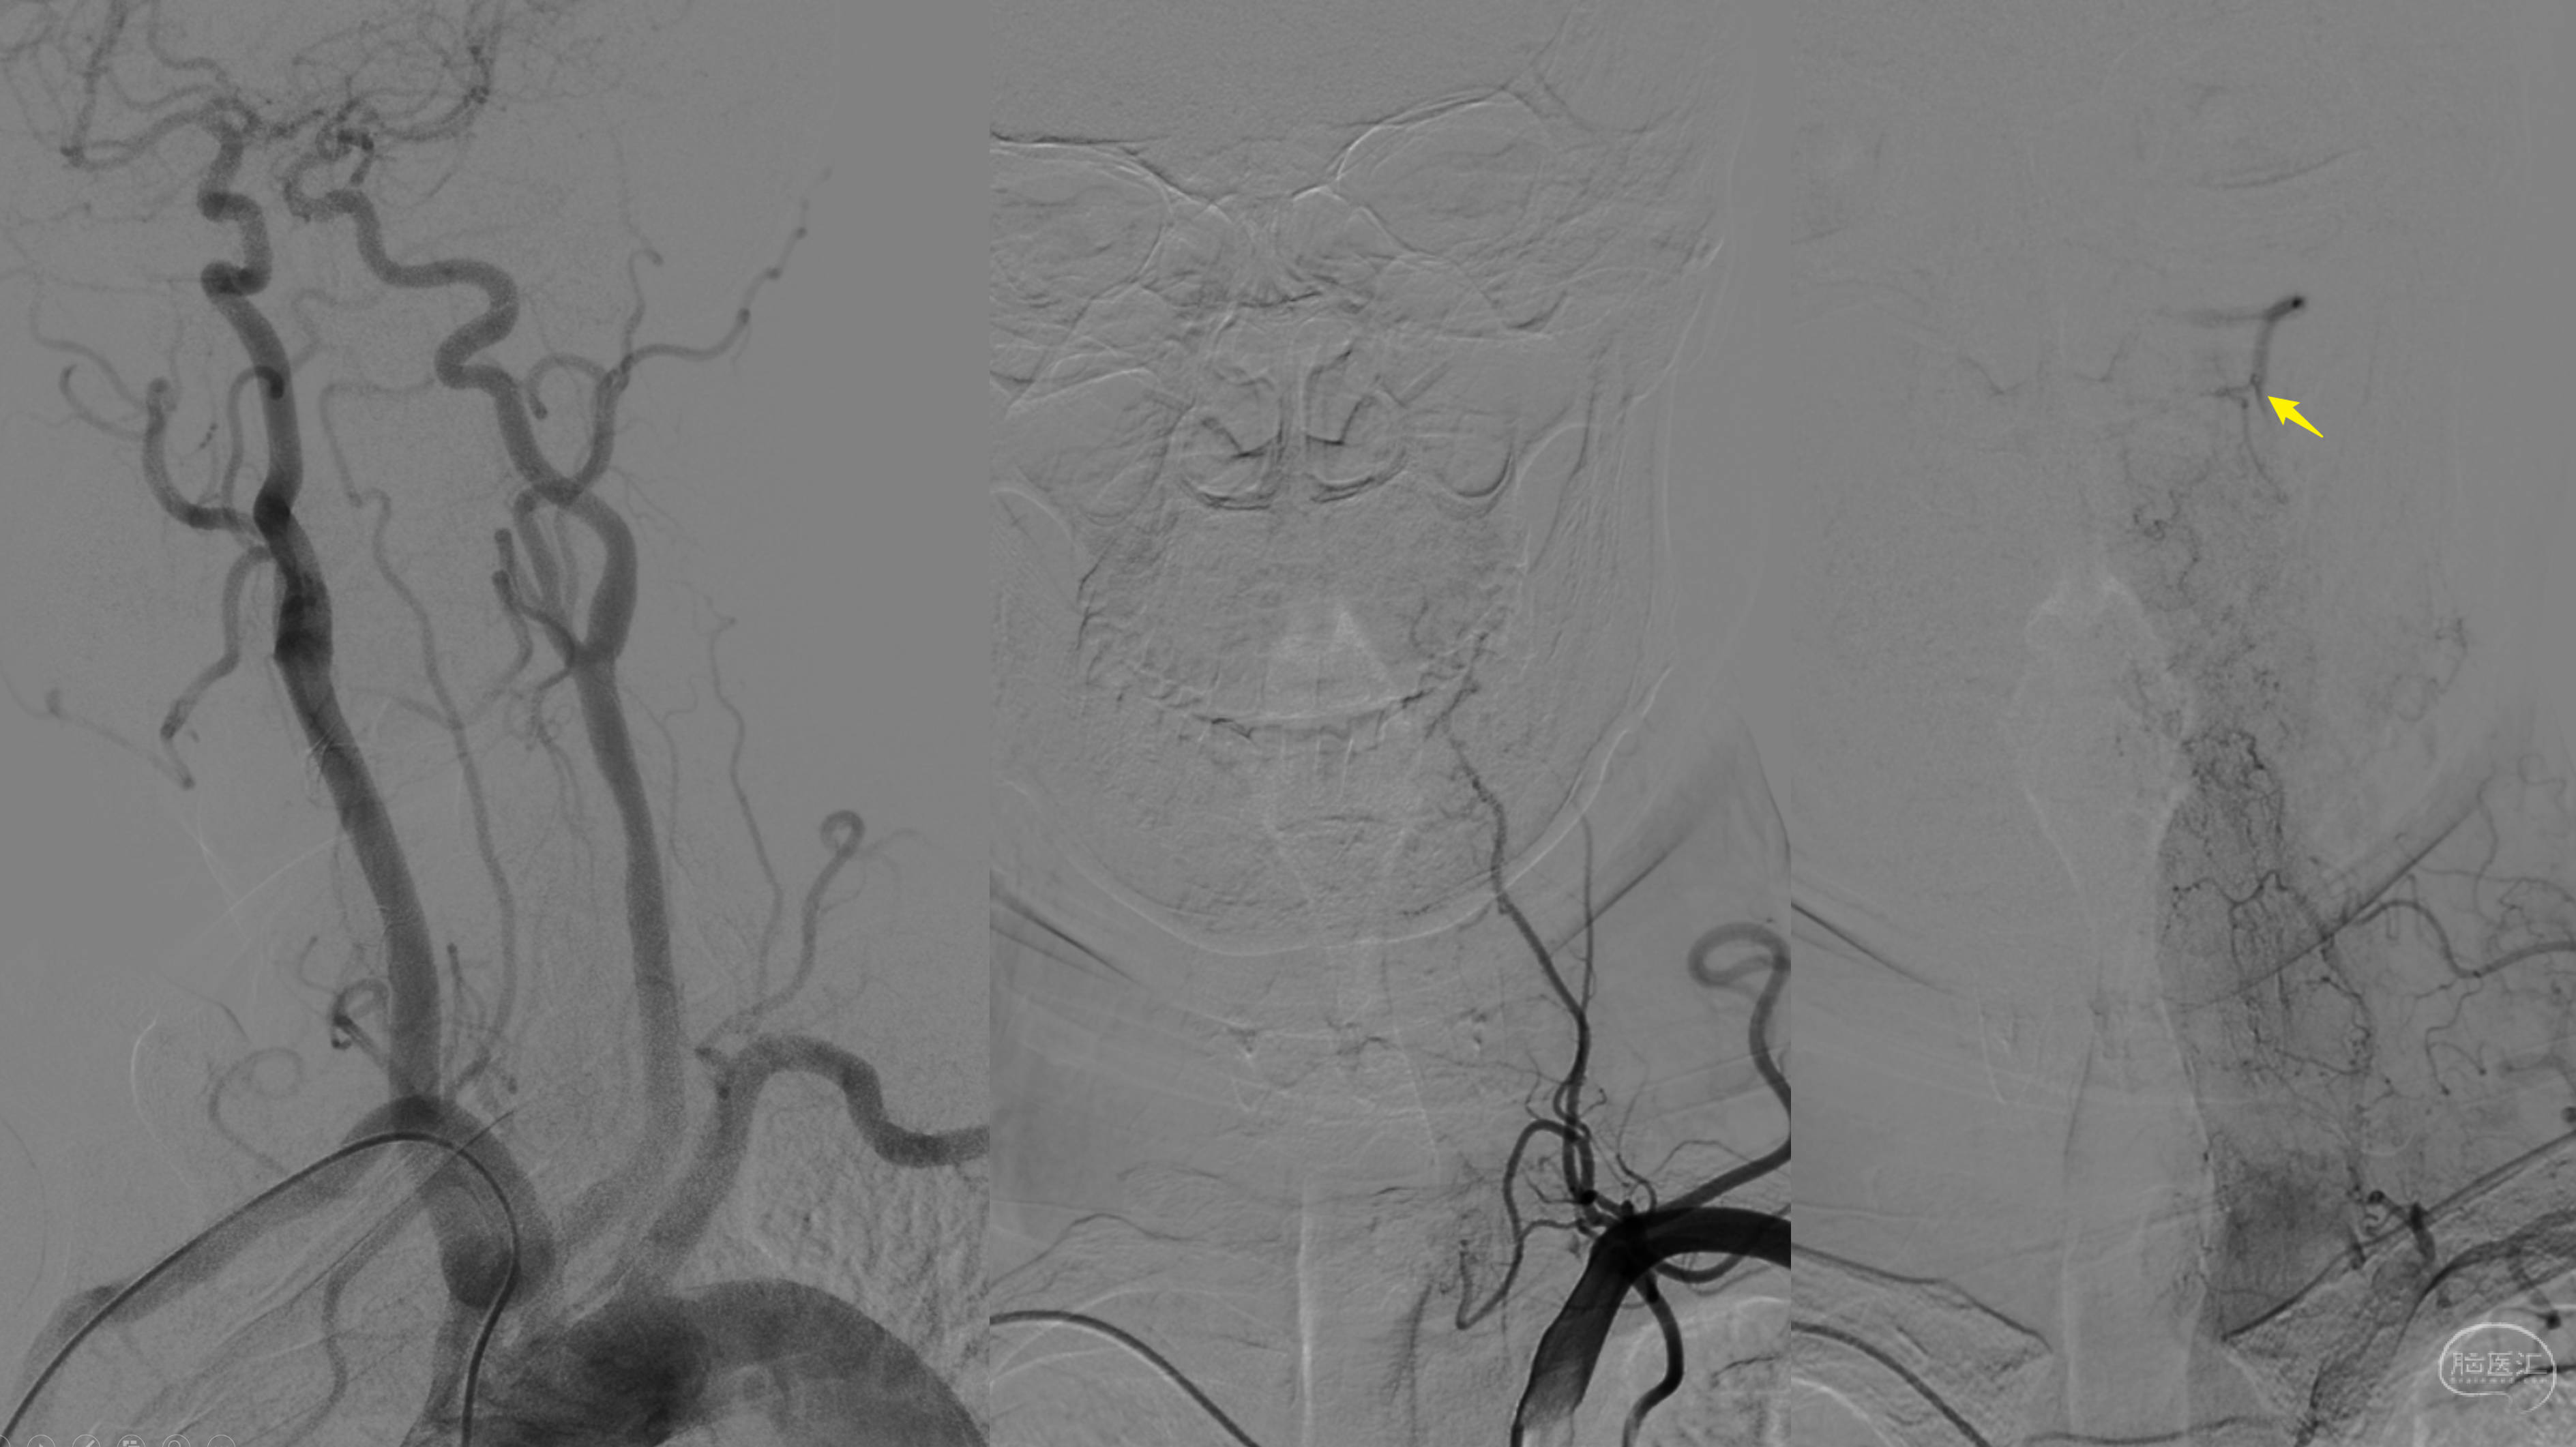

DSA造影看到左侧椎动脉V3段通过颈深动脉的肌支吻合代偿供血,但显影一般。

前循环造影提示以后交通开放,向后循环代偿。

右侧ICA主要代偿右侧大脑后动脉。

右侧椎动脉非优势,颅内段发育不良。

外院曾尝试开通,因起始部完全闭塞,不成功!